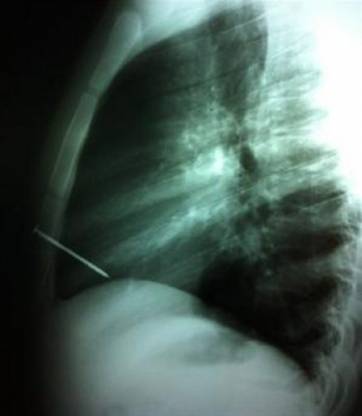

Los profesionales explicaron que el clavo, de ocho centímetros de largo, atravesó el esternón y el ventrículo derecho del corazón, y quedó alojado en la cavidad cardíaca.

El lunes, este joven de 19 años, al que sólo se lo identificó como Ariel, recibió el disparo de una pistola neumática que manipulaba un compañero, mientras realizaba su labor habitual en una fábrica de pallets de madera de localidad de Cañuelas. De inmediato fue llevado al Hospital ‘Dr. Angel Marzetti‘ de esa ciudad, donde le realizaron una placa de tórax y observaron que el clavo estaba alojado en el corazón.

Con ese diagnóstico fue trasladado al Hospital El Cruce, donde llegó cerca de la medianoche e inmediatamente le practicaron una tomografía computada que confirmó la herida penetrante cardíaca. El diagnóstico obligó a los médicos a realizar de urgencia la extracción del clavo y la cirugía de reparación cardíaca.